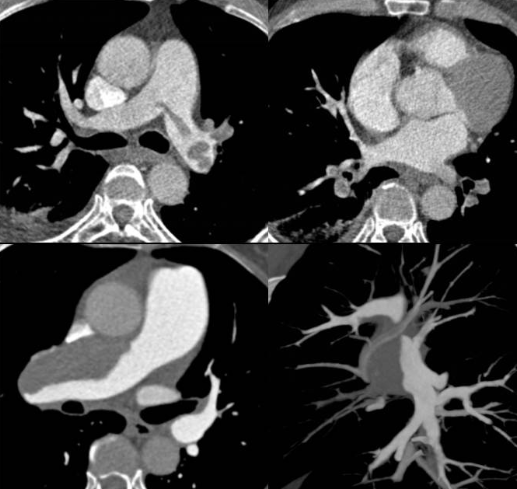

肺动脉CT血管造影(CTPA)

肺动脉CTA是利用CT扫描下的肺动脉造影,优点是基本无创,几分钟就能很好的显示中央及周围肺动脉血管分支情况,通过不同的后处理技术,将肺动脉解剖及病变直接显示出来,是发现肺栓塞的利器。